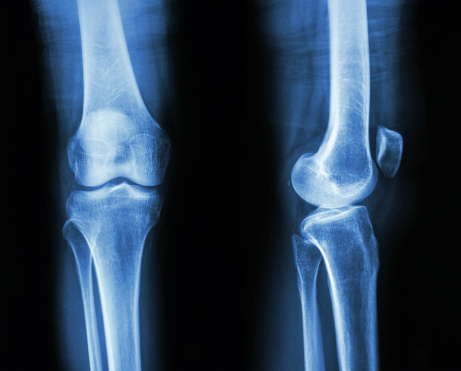

가족이 소년을 병원에 데려가 검사를 해보니 엑스레이 사진에서 성장판이 완전히 골화된 것으로 나타났다. 나이는 15세에 불과하지만 뼈 나이는 이미 18세 수준으로, 성장이 사실상 멈춘 상태라는 의미였다.

성장판은 뼈 끝부분에 있는 연골 층으로 뼈가 길게 자라는 통로 역할을 한다. 하지만 성장이 다 완료되면 연골인 성장판이 단단한 뼈로 변한다.